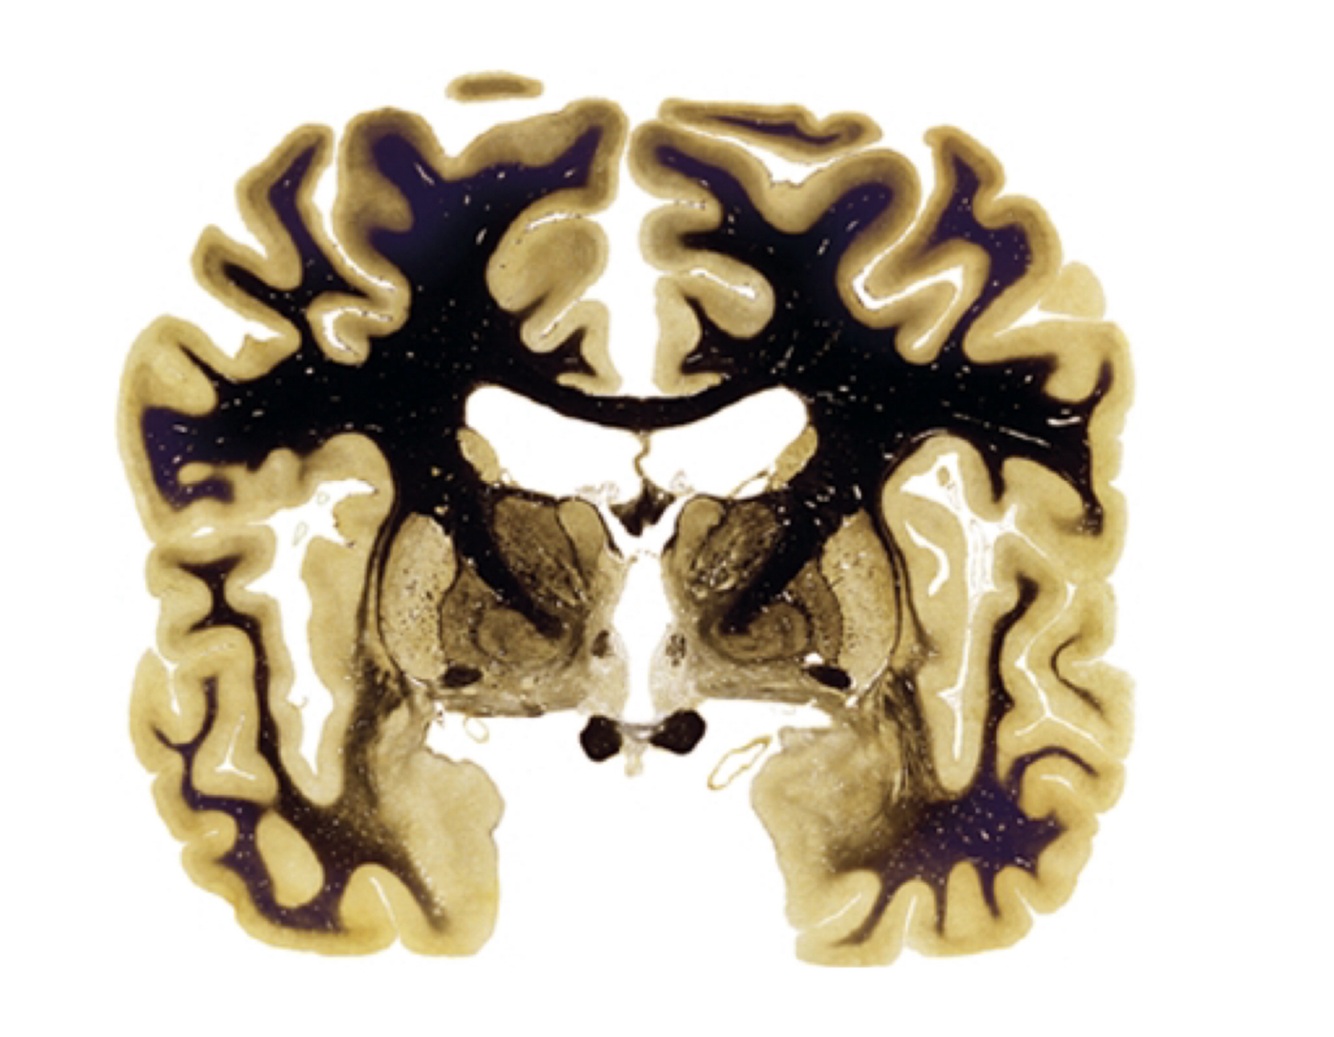

In some images, which are not fresh and are stained, white matter appears as…

Black

In brain, the gray matter is in the…

Cerebral cortex

What do ventricles contain? How many do we have?

Cerebrospinal fluid. We have 4.

All the information that has to go to the cortex, passes before by the…

Thalamus